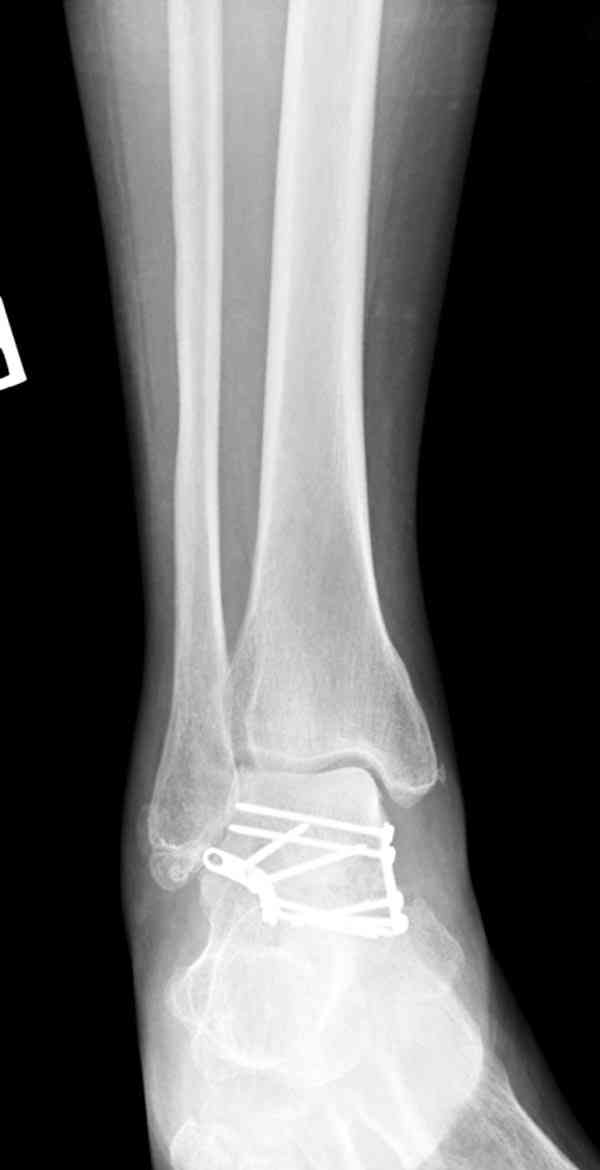

Случай с множественным оскольчатым переломом тарана оперированный из двойного доступа.

Через 14 мес.: